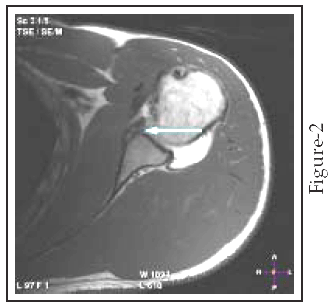

At arthroscopy, 21 anteroinferior labroligamentous lesions were diagnosed, including 15 Bankart lesions Fig (1,2),3 ALPSA lesions(Fig-3), 2 Perthes lesions (fig-4), and 1 GLAD lesion (Fig-5). Seven labral lesions were nonclassifiable at arthroscopy, all of which occurred after a history of chronic instability. When compared with arthroscopic findings, Shoulder MR Arthrography had two false-negative results (sensitivity, 92.8%) and no false-positive results. The sensitivity of Shoulder MR Arthrography in detecting anteroinferior labroligamentous lesions was 92.8% (26/28), and specificity was (100%). The overall accuracy of Shoulder MR Arthrography in detecting labroligamentous lesions in our study was 90.5% (19/21).

Fig-2: Bony Bankart Lesion. An axial T1 weighted spin echo MR arthrogram in a 31 years male patient with history of recurrent anterior shoulder dislocation .It shows fracture through the anteroinferior aspect of the bony glenoid together with an avulsed anteroinferior labrum (arrow) which is referred to as an osseous Bankart lesion.